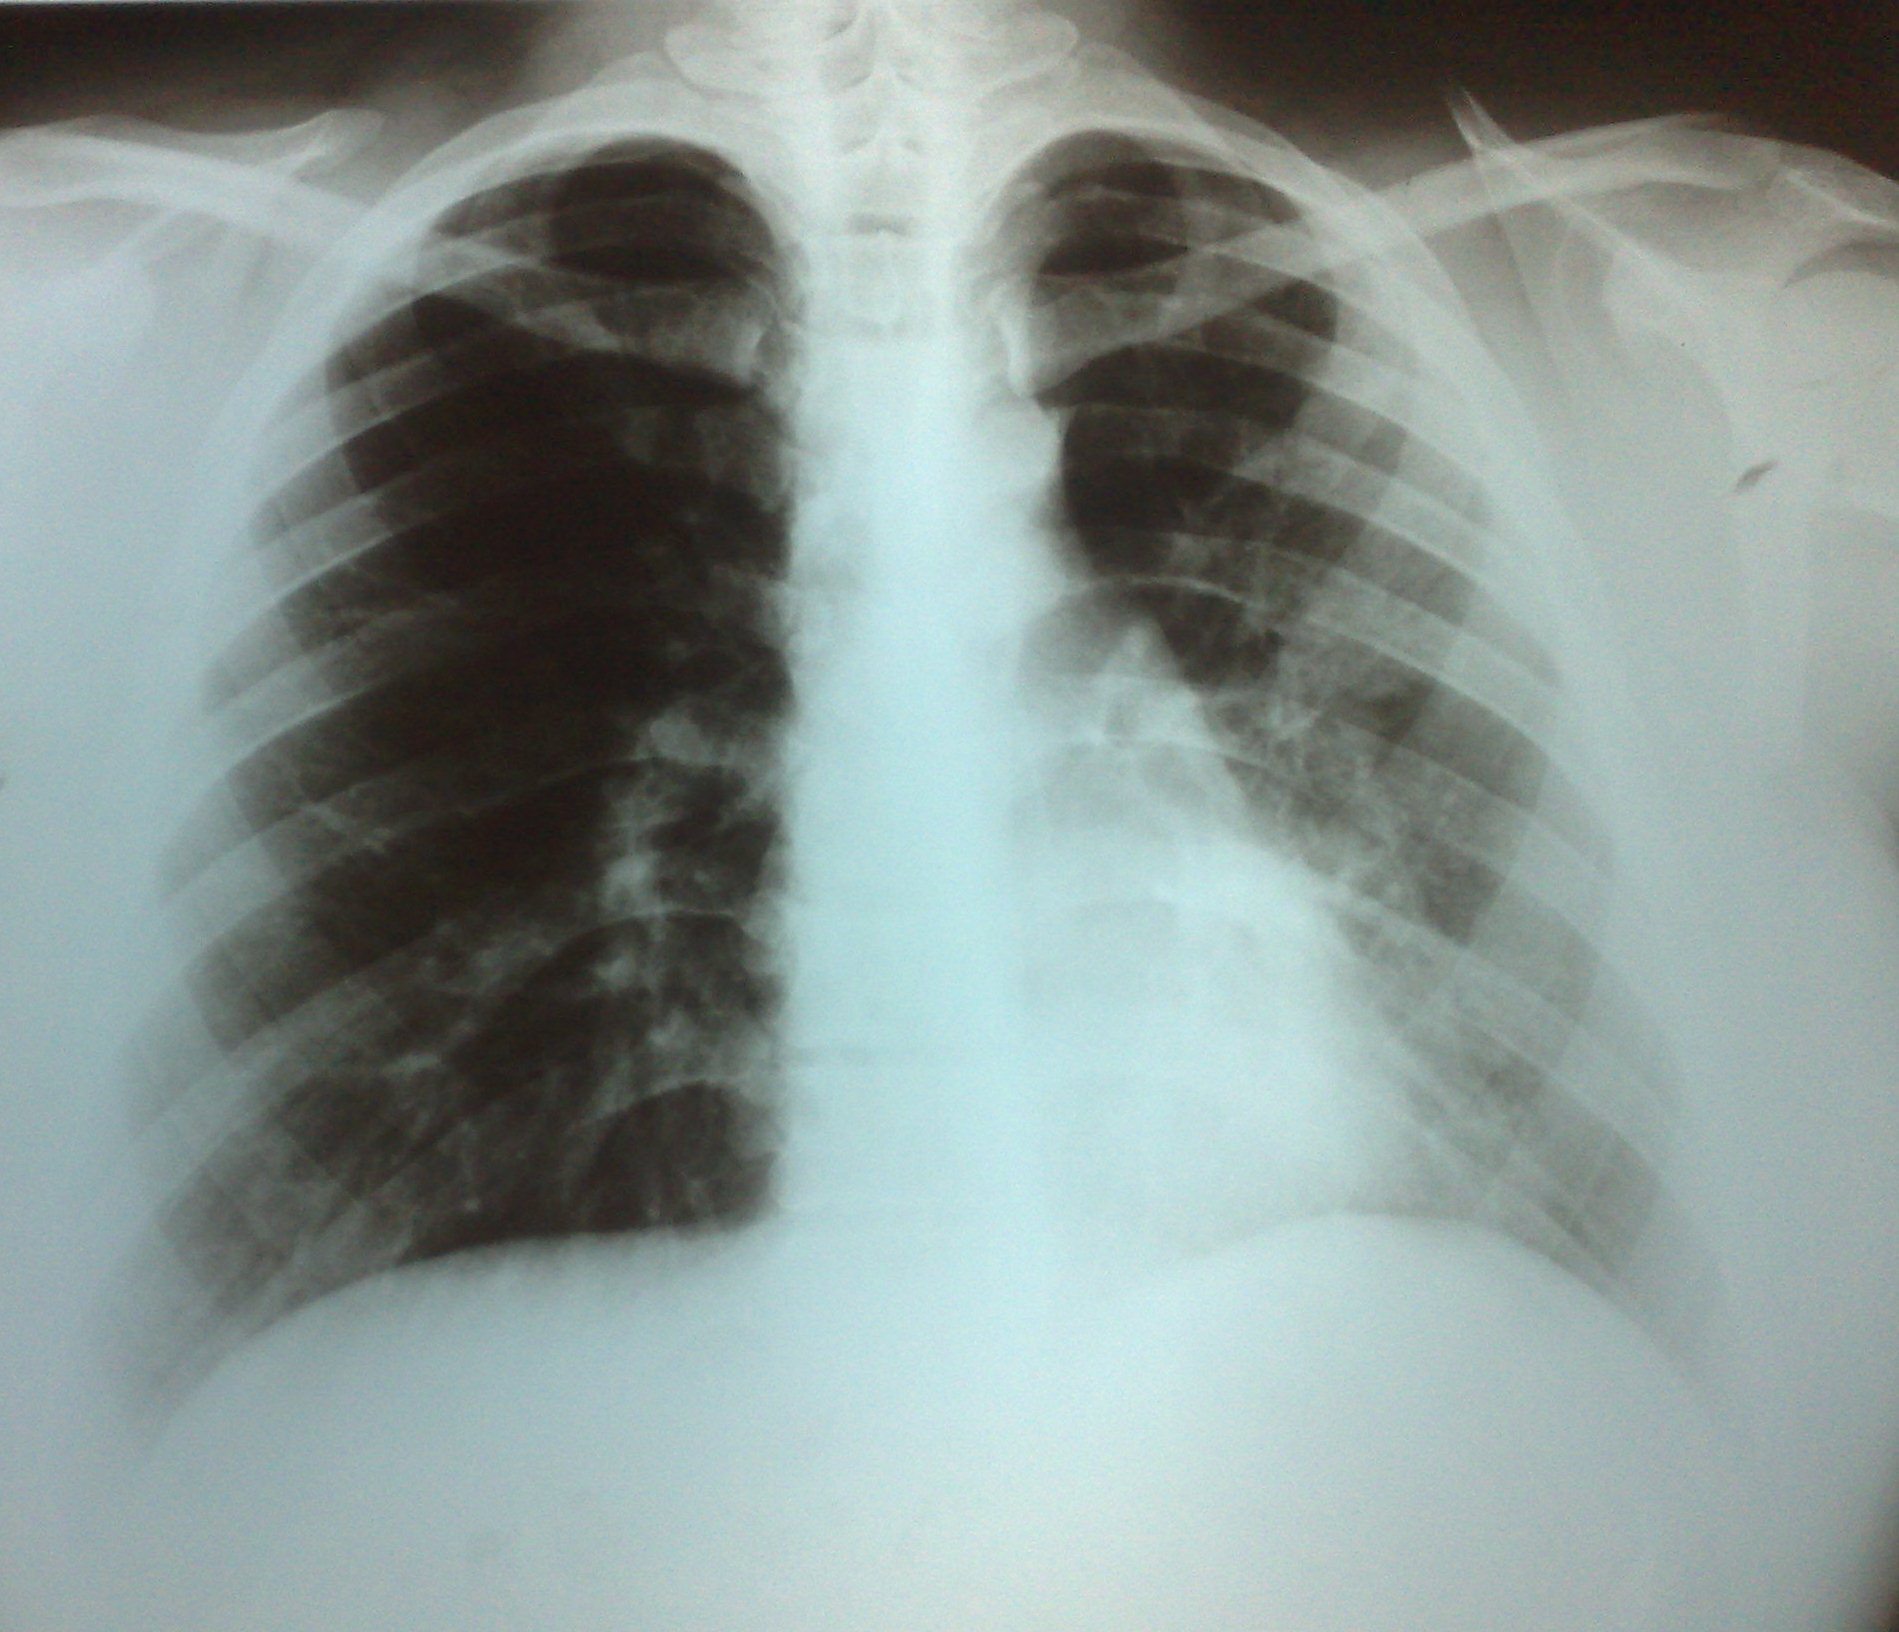

- გულმკერდის რენტგენოგრაფია სტენტირებამდე 10 დღით ადრე

აღინიშნება მარცხენა ფილტვის ჰიპოვენტილაცია და შუასაყარი საგრძნობლად ცდომილია მარცხენა მხარეს.